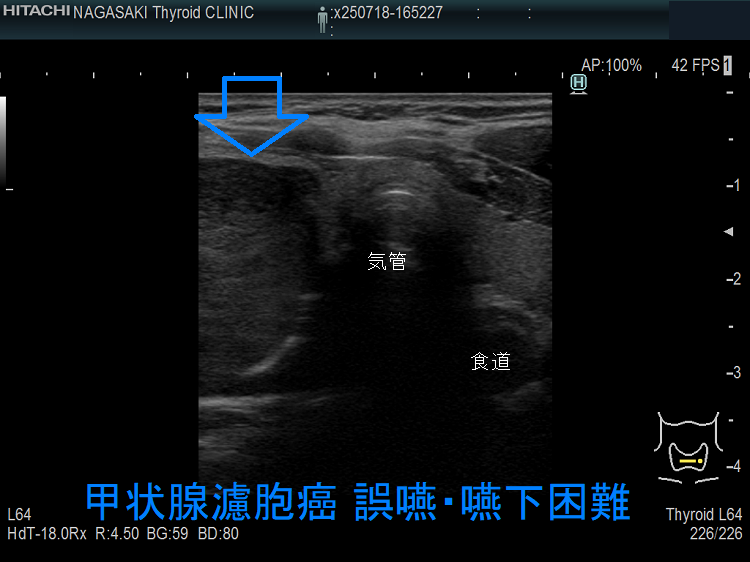

食道を圧迫する巨大甲状腺のう胞腺腫;食道は背側へ圧排され、嚥下障害・誤嚥を来したケース。

喉(のど)の違和感、喉(のど)に引っかかる感じ、嚥下時の違和感があっても、巨大な甲状腺腫瘍や小さくても甲状腺癌の場合を除けば、嚥下障害に至る甲状腺疾患は稀です。

ただし、例外はあって、気管・食道を圧迫する程の

では嚥下障害も起こります。